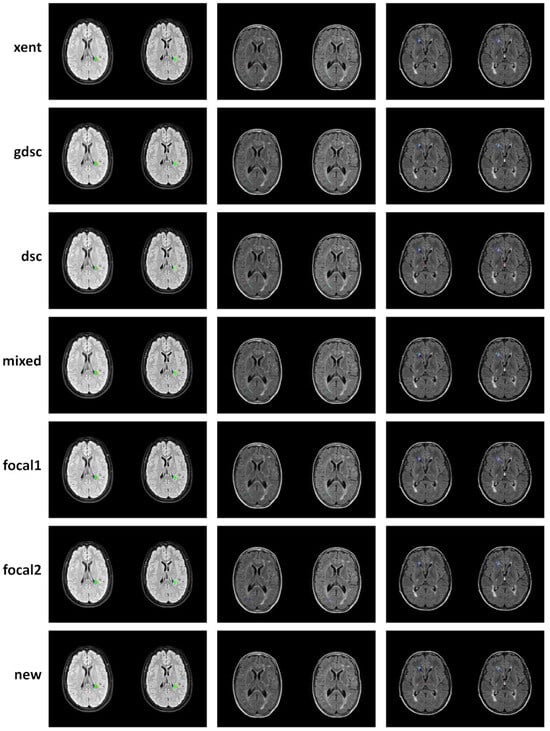

| xent | 0.96 | 0.68 | 0.42 | 0.95 | 0.60 | 0.55 | 0.97 | 0.80 | 0.47 |

| gdsc | 0.86 | 0.71 | 0.69 | 0.85 | 0.64 | 0.63 | 0.88 | 0.79 | 0.76 |

| dsc | 0.88 | 0.56 | 0.54 | 0.87 | 0.55 | 0.65 | 0.89 | 0.60 | 0.60 |

| mixed | 0.89 | 0.56 | 0.44 | 0.89 | 0.58 | 0.63 | 0.90 | 0.62 | 0.47 |

| focal1 | 0.94 | 0.71 | 0.68 | 0.91 | 0.64 | 0.59 | 0.97 | 0.80 | 0.81 |

| focal2 | 0.96 | 0.72 | 0.72 | 0.98 | 0.72 | 0.69 | 0.94 | 0.73 | 0.75 |

| new | 0.79 | 0.70 | 0.71 | 1.00 | 0.85 | 0.81 | 0.65 | 0.61 | 0.63 |